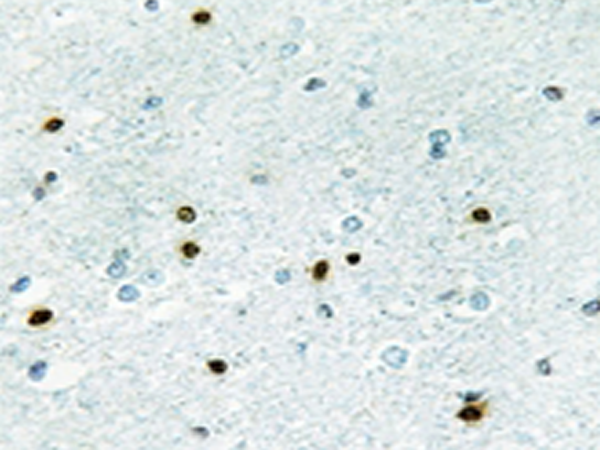

IHC positive control: |

Human brain tissue |

IHC Recommend dilution: |

50-100 |